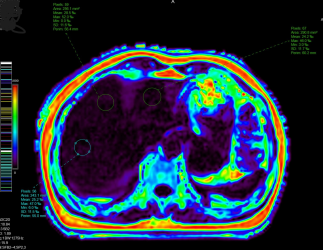

基于水脂分离技术获取PDFF图的方法则比较实用,属于无创性检查,也是目前医学影像科正在开展的评定肝脏脂肪的方法。此技术能全面检查肝脏,扫描时间短,后处理方便。稳定性、准确度、精密度高,被认为是评估肝脏脂肪含量的客观有效方法,可为脂肪肝的早期诊断、分级、治疗策略选择和预后评估提供重要的信息。

在PDFF图勾画多个感兴趣区测量相应PDFF值以评估脂肪肝程度